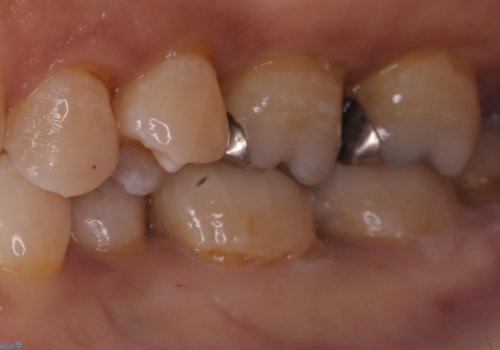

左下7番目の歯の詰め物が外れ、セラミックインレーでのやり替えとなりました。

隣在歯にも保険適用もメタルインレーが入っており、咬合面のインレーと歯質の境目が虫歯になっていたこともあり、合わせてのやり替えとなりました。

左下7番めの歯、フロスを通したらインレーが外れてしまったとのことで、適合具合の精密さや、これを機に白い詰め物にしたいとのことからセラミックインレーでのやり替えとなりました。

また、6番目の歯にも保険適用のメタルインレーが入っており、咬合面インレーと歯質境目にう蝕を認め合わせてのやり替えとなりました。